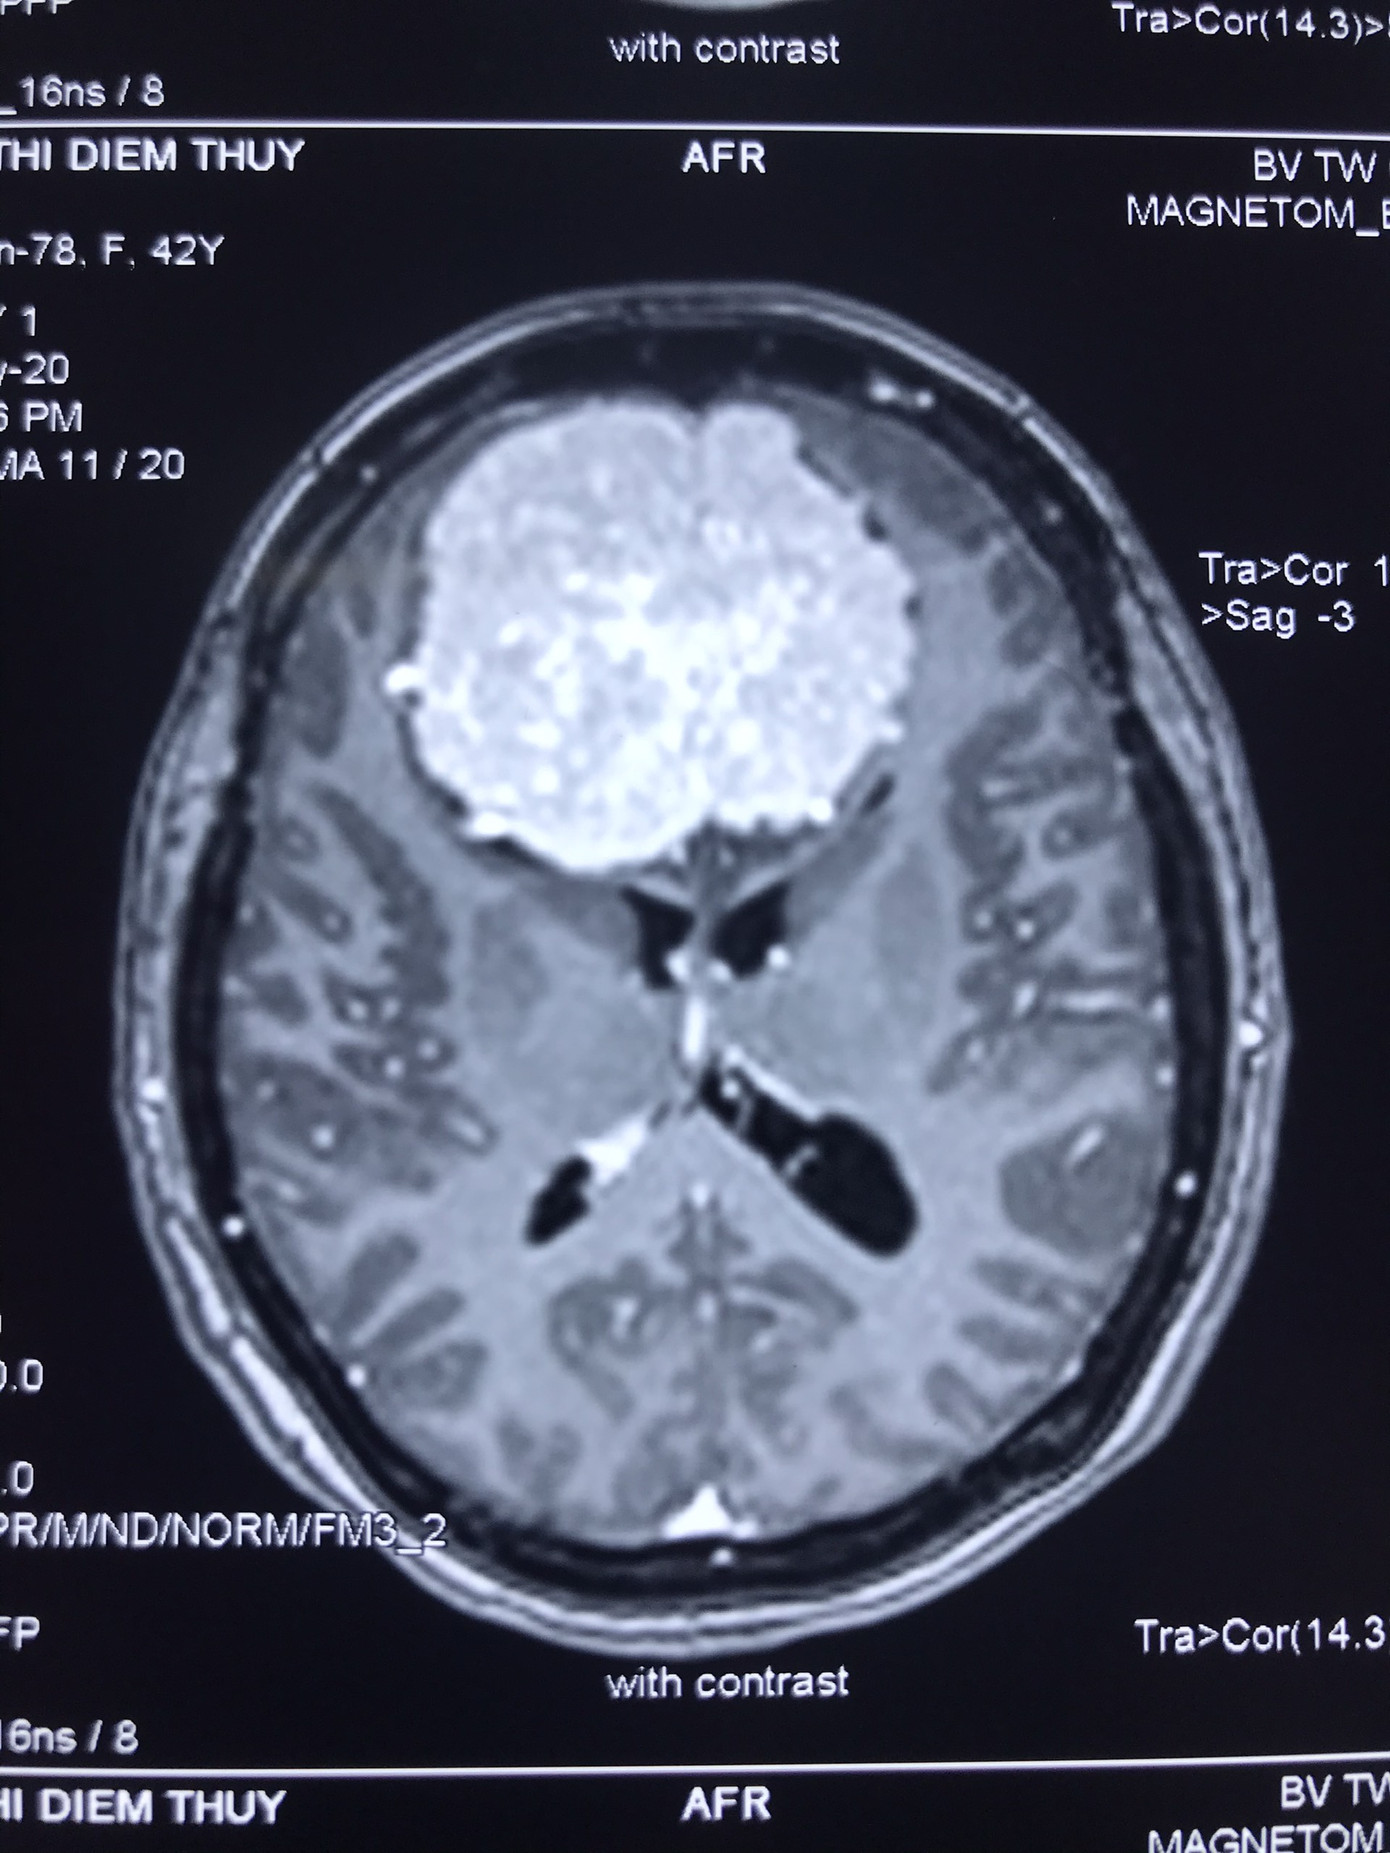

Hình ảnh khối u khổng lồ trong não của chị Thúy. Chị Thúy nhập viện trong tình trạng đau đầu nhiều, thị lực hai mắt giảm, nhìn đôi, phù gai thị, mất mùi hoàn toàn.

Kết quả chụp cộng hưởng từ có tiêm chất tương phản từ ghi nhận, khối choáng chỗ ngoài vùng trán có kích thước 6x6.5x5cm, ép não thất hai bên.

Kết luận, đây là u màng não khổng lồ. Sau khi hội chẩn, bệnh viện quyết định chụp và nút mạch tiền phẫu số xóa nền nhằm mục tiêu tắc mạch máu nuôi khối u, rồi tiến hành phẫu thuật vi phẫu bóc tách khối u màng mão rãnh khướu sàn sọ.